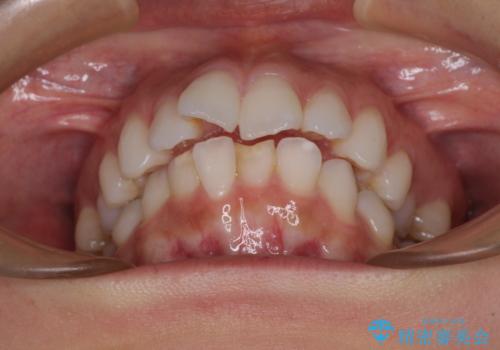

- 口元の突出感を気にして来院された患者様です。

左右ともに奥歯の咬み合わせに問題があり、上顎臼歯が前方位にある状態で、結果として上顎前歯全体が前方位かつ叢生になっていました。

埋伏している右下第二大臼歯は、牽引して咬合に参加させることで計画しましたが、癒着などにより移動困難な場合には、抜歯の上インプラント補綴治療を行うこととしました。

右下の埋伏歯はやはり癒着しており、抜歯の後にインプラントを埋入することとなりました。

埋伏歯の牽引や、奥歯の咬み合わせ改善、インプラント補綴治療と治療期間が延びてしまう要素が多く、治療は難航しましたが、最終的に非常に満足のいく仕上がりとなりました。